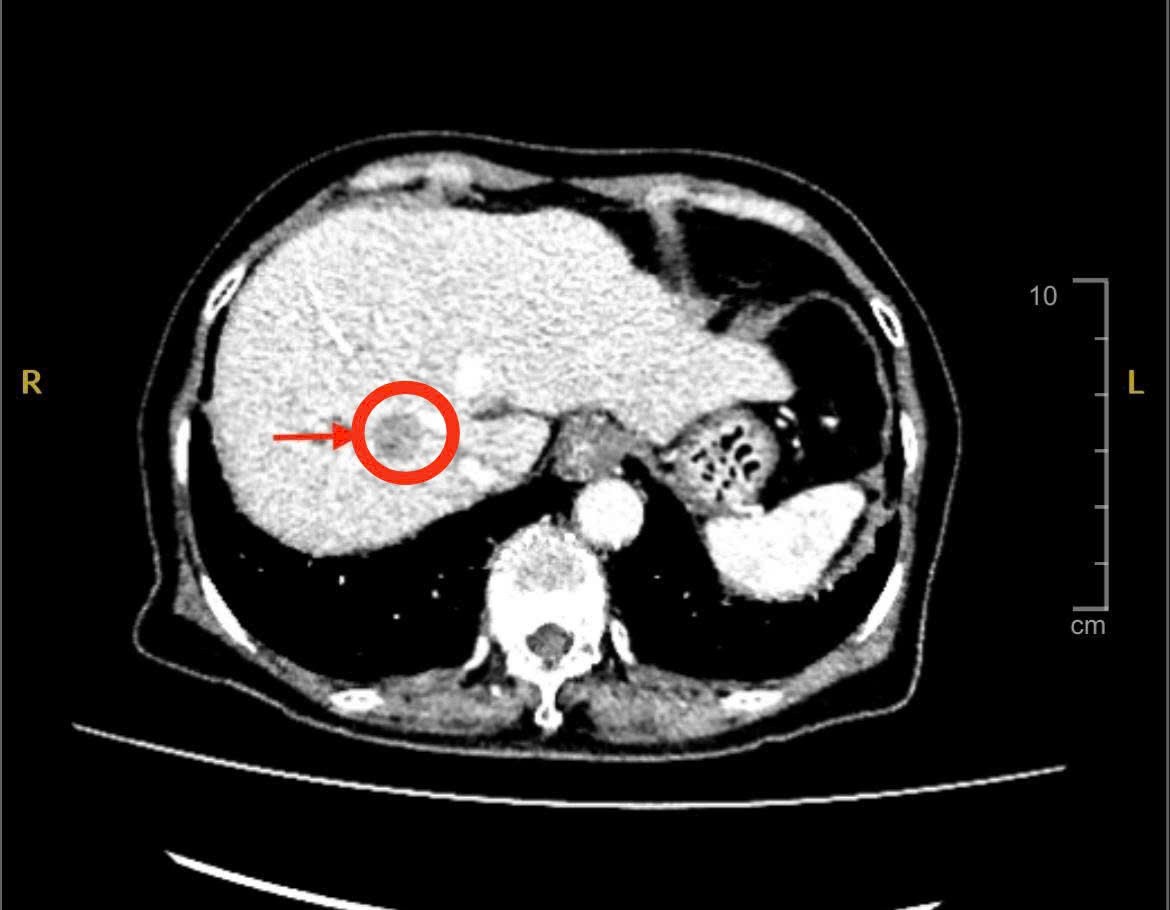

Tại đây, kết quả siêu âm bụng và chụp MSCT phát hiện khối u gan phải kích thước khoảng 2 cm, nghi ngờ ung thư nguyên phát tế bào gan (HCC) – dạng ung thư gan phổ biến ở người có bệnh nền xơ gan, viêm gan B hoặc viêm gan C.

Hình ảnh CT khối u gan (Ảnh:BVCC)